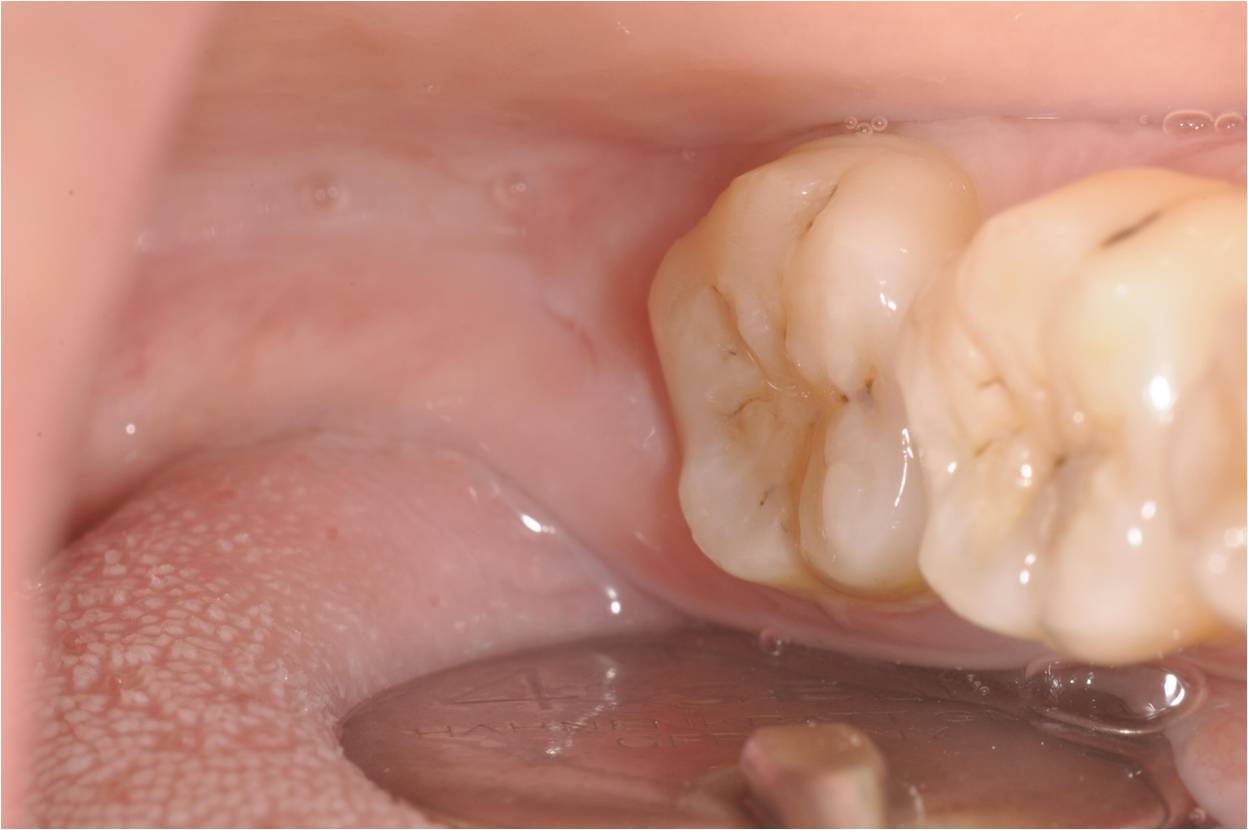

左下阻生齒術前口內狀況